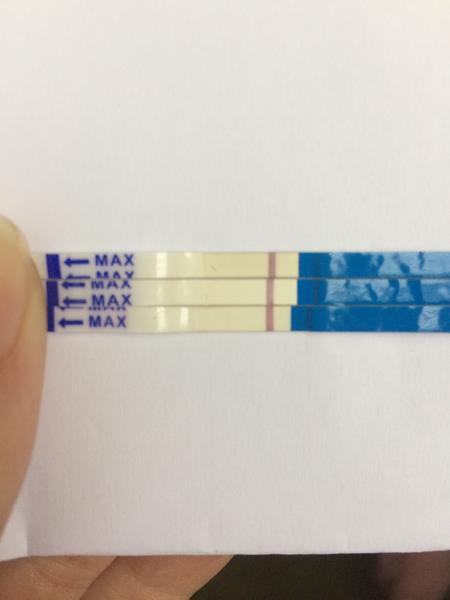

První byl ClearBlue a téměř hned tam naskočilo plus.

Udělal jsem radši ještě jeden - jmenuje se ForYou... Tam se objevil slabý duch, ale až tak za 3minuty! Šla jsem ven se psi a když jsem se vrátila, tak duch byl silnější...no ale to bylo skoro po půl hodině!

Tak nevim ... ☹ Dávám fotku, skuste posoudit...

- Slabá druhá čárka na domácím těhotenském testu může znamenat velmi časné těhotenství, biochemické těhotenství nebo vliv ředění moči a různou citlivost testů; spolehlivější potvrzení poskytne opakované testování z první ranní moči a krevní odběr hCG.

- V diskuzi byly zmíněny konkrétní citlivosti testů (ClearBlue 25 mIU/ml, ForYou 20 mIU/ml, RapidClear 10 mIU/ml) a zároveň varování, že intenzita čárky závisí na značce, množství barviva v testu a koncentraci moči, takže srovnávání čárek mezi různými testy je nespolehlivé.

A: Intenzita čárky závisí na koncentraci moči (nejkoncentrovanější je ranní moč), na množství barviva v konkrétním testu a na množství hCG v krvi; v diskuzi také zaznělo, že čárka může být slabá v časném těhotenství nebo při biochemickém těhotenství.

A: Několik příspěvků varovalo, že čtení výsledků mimo doporučený čas může ukázat „ducha“ vlivem zaschnutí nebo chemických reakcí; spolehlivý výsledek je ten uvedený v návodu testu v doporučeném časovém okně.